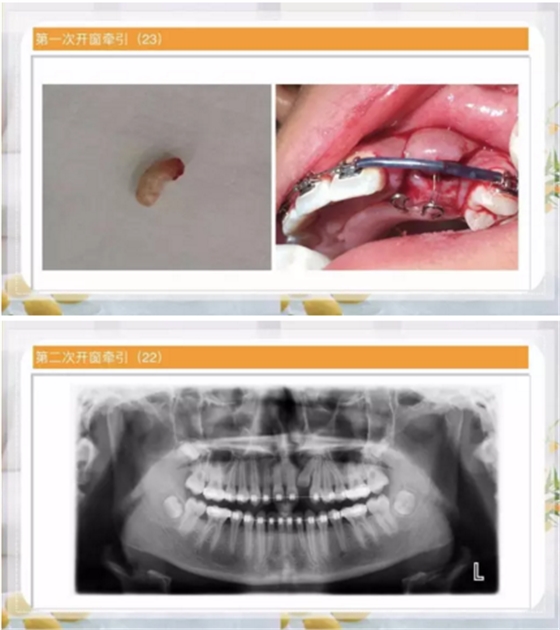

第一種方法:糾正過(guò)來(lái)!

阻生齒外科聯(lián)合正畸治療